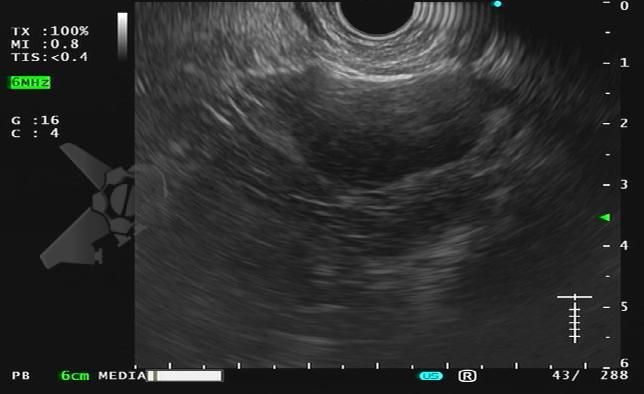

Durante el examen de ecoendoscopia, fue identificada la imagen en la adrenal isquierda:

Ante este hallazgo incidental, ¿cuál sería su conducta?

- Punción ecoguiada con FNA

- Punción ecoguiada con FNB

- Discusión multidisciplinar